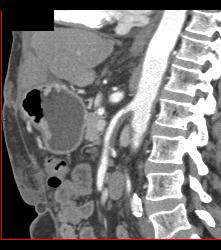

Intramural Hematoma